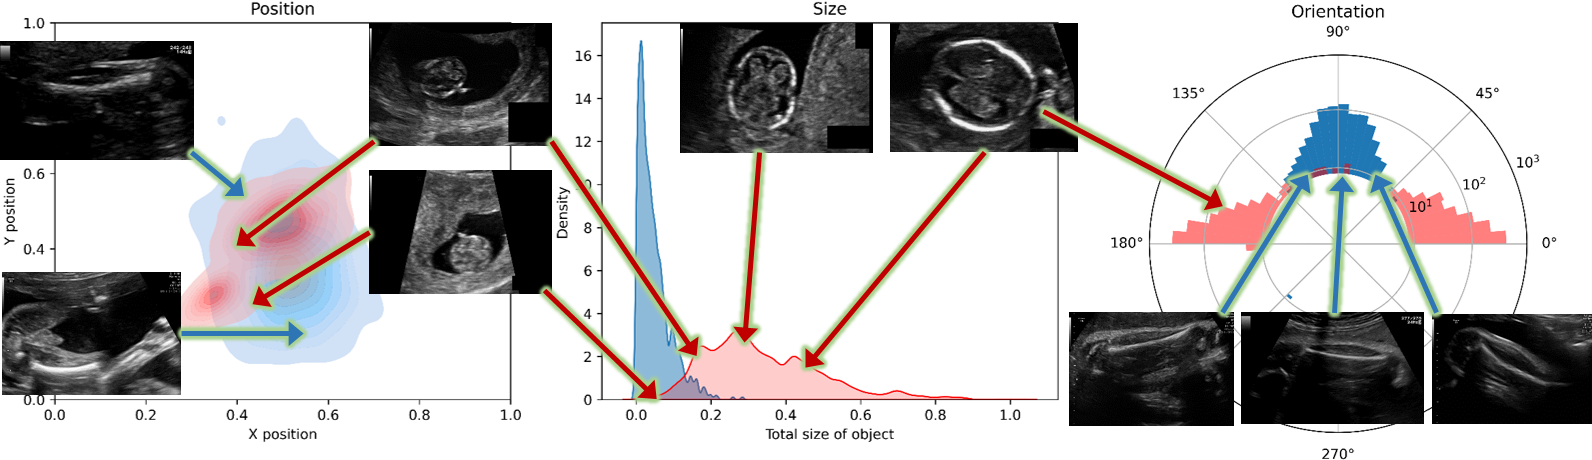

Study 3: Impact of training dataset: to demonstrate the generalization capabilities of BiometryNet, we analyzed its performance by cross-validation on unseen datasets. For this purpose, we train the OFD and BPD models on FP dataset and test each on HC18 dataset, and vice versa. Table 1 lists the results. Note that training on one dataset and testing on the other (rows 6 and 12) results in high mean and median errors, with significant and complementary (2.31mm vs -3.24mm in OFD, 0.81mm vs -1.11mm in BPD) bias and acceptable variance. In contrast, testing on the same dataset (rows 5 and 11) results in low bias, but similar variance (CI95𝐶subscript𝐼95CI_{95}) as before. This bias can be explained by the differences in annotation protocol between the two datasets. In HC18, the landmark annotations lie between the outer contours of the skull, while in FP, they are marked in the middle of the fetal skull contour, thus resulting in a consistent bias (Fig. 2 supp.). Clinically, both protocols are acceptable, and their selection depends on the specific clinical site. We also observe that using FP annotations for network training produced better and more consistent results than using those of HC18. This may occur because HC18 annotations are extracted from HC ellipse rather than annotated directly at the BPD/OFD landmarks. We conclude from these results that BiometryNet is capable of generalization, as it can learn to annotate like the annotation protocol, and can be tuned for use across many sites and protocols.

Refer to caption

Figure 6: Example showing different results of two annotation methods and the resulting BiometryNet predictions. Two models were trained, one on the FP training dataset (first column) and the second on the HC18 training dataset (second column). Both were run on the FP testing dataset (first row) and the HC18 testing dataset (second row). Landmarks are marked in the middle of the fetal skull in FP dataset and on the outer extrema of the skull in HC18 dataset. This introduces a bias that results in a relatively larger error, although still within the clinically acceptable limit when generalizing from FP\rightarrowHC18 or HC18\rightarrowFP. The quantitative results are presented in Table 1 and discussed in Study 2 and 3. The images show ground truth annotations (blue) and computed predictions (green) on representative examples of BPD biometry. The relevant areas are enlarged in the yellow box.